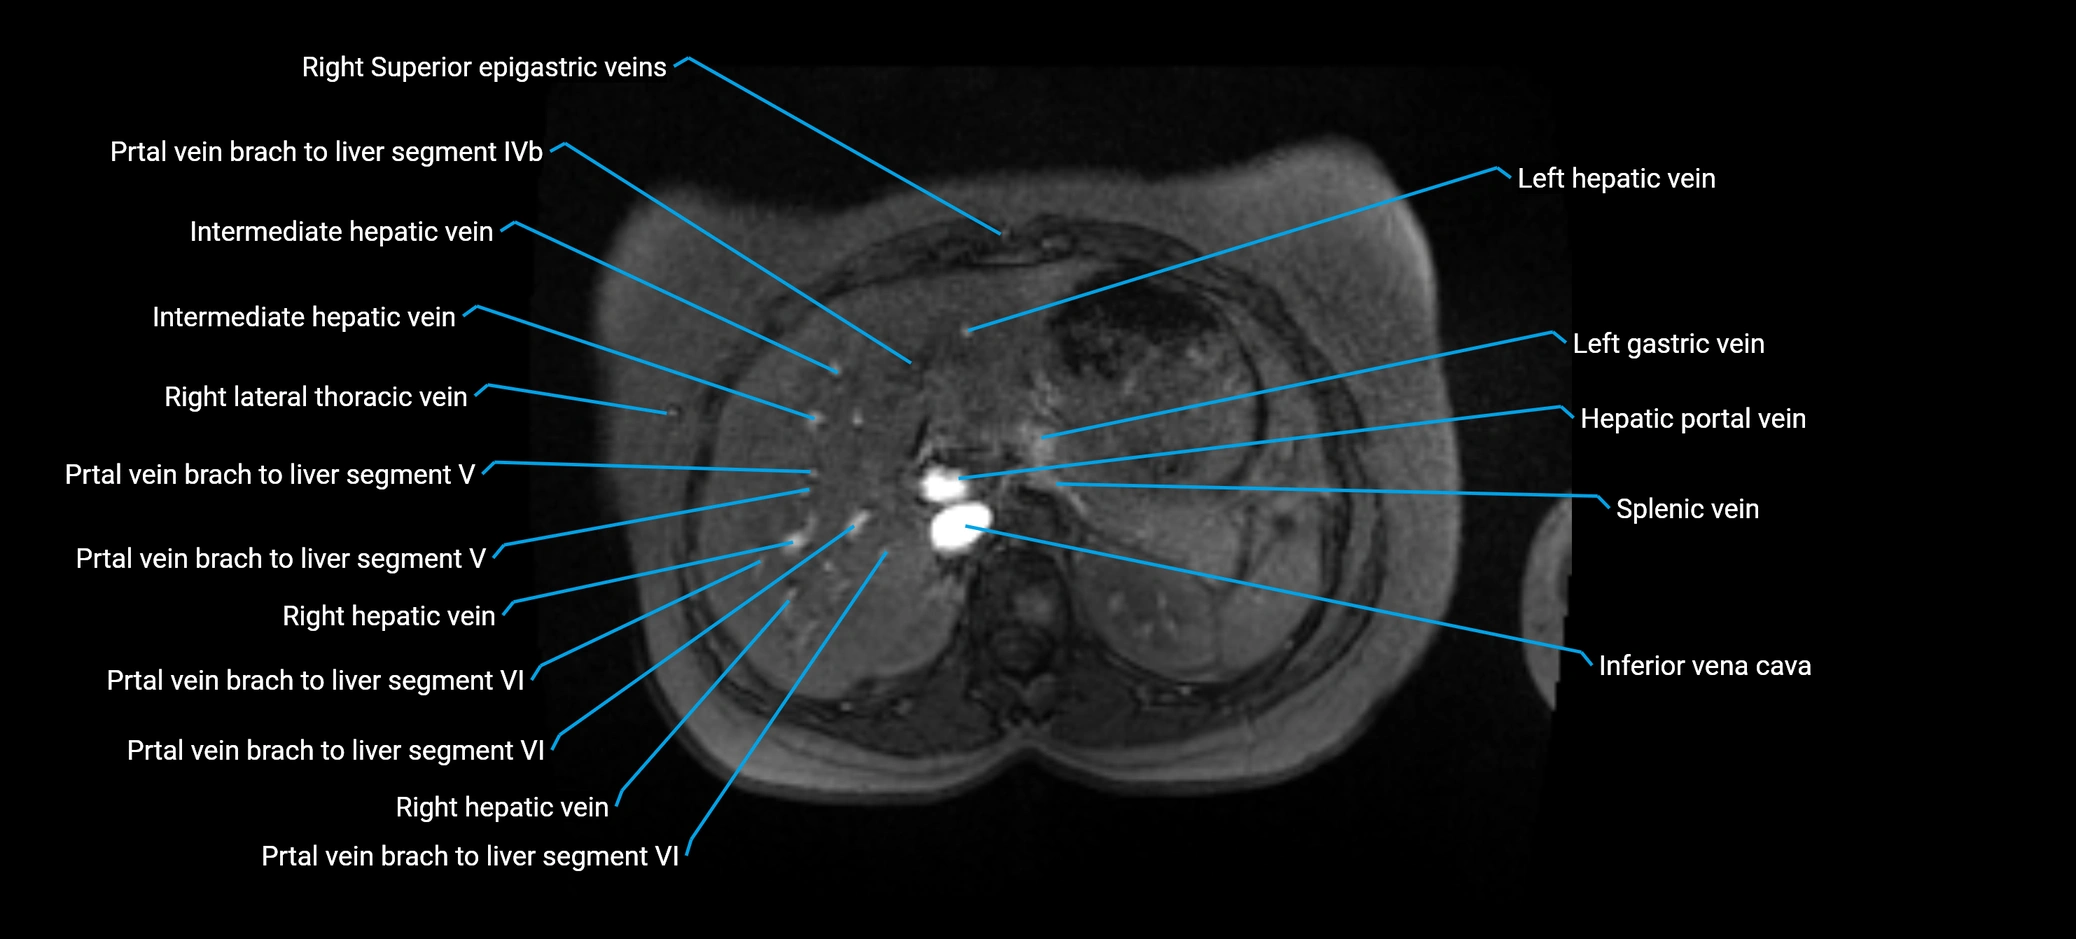

MRV TOF (Time-of-Flight MR Venography):

• Appears as a bright, high-signal vascular channel representing flowing blood

• Clearly shows branching pattern of right portal vein into anterior and posterior branches

• Best in coronal or axial reconstructions for segmental mapping

• No need for contrast, relies on flow-related enhancement

• Clearly delineates branching into segments V and VIII

• Best sequence for evaluating patency, caliber, and anatomic variants